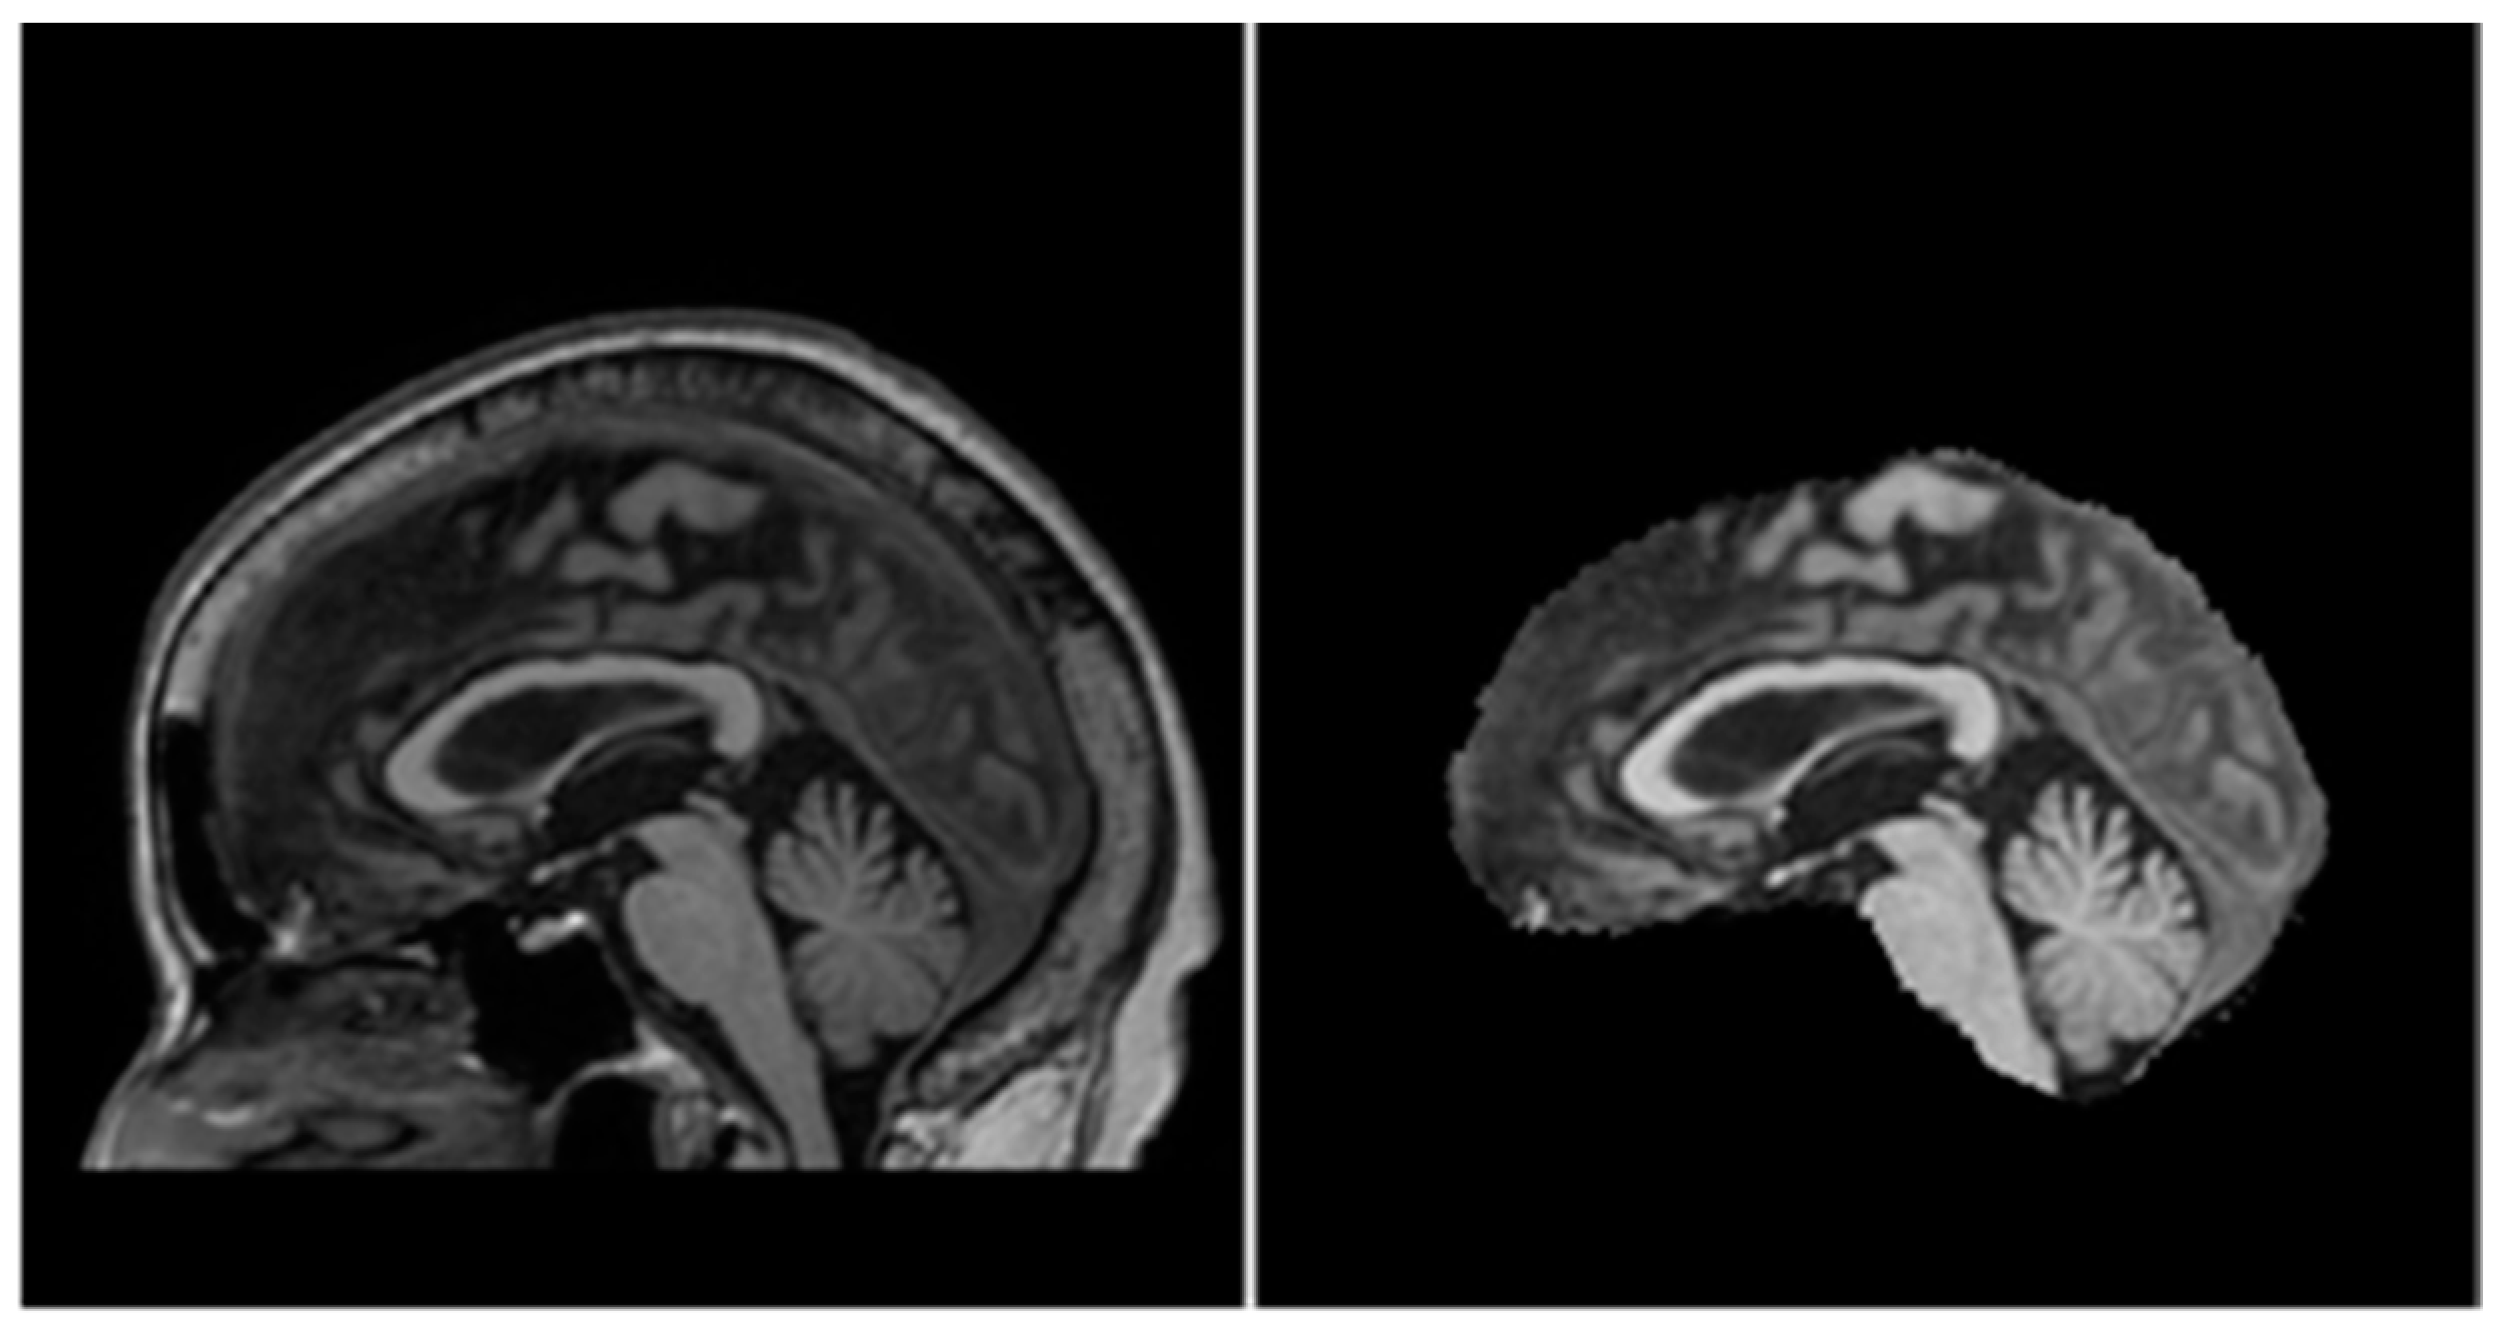

As mentioned above, 2D convolution models process volumetric MRI data by going through them slice-by-slice. In 3D MRI scans, there are three main orthogonal axes from which slices may be taken as shown in Figure 2. Therefore, most 2D convolution models adopt a multi-view approach in which they combine the outputs of several networks with different views to form a final predicted segmentation of the hippocampi.

Figure 2.

From left to right: sagittal, coronal, and axial view of an MRI volume. Left and right hippocampi are highlighted in green.